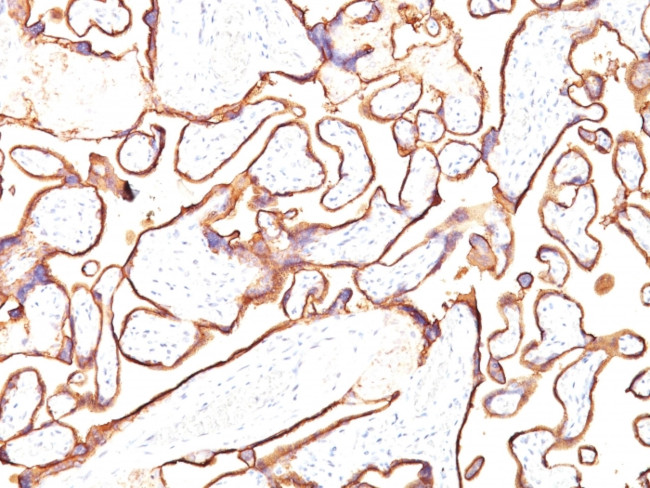

Alkaline Phosphatase (Placental)/PLAP (Germ Cell Tumor Marker) Antibody in Immunohistochemistry (Paraffin) (IHC (P))

图: 1 / 2

Alkaline Phosphatase (Placental)/PLAP (Germ Cell Tumor Marker) Antibody (250-MSM5-P1ABX) in IHC (P)

Formalin-fixed, paraffin-embedded human Placenta stained with PLAP Monoclonal Antibody (PL8-F6). {{ $ctrl.currentElement.advancedVerification.fullName }} 验证信息 View more